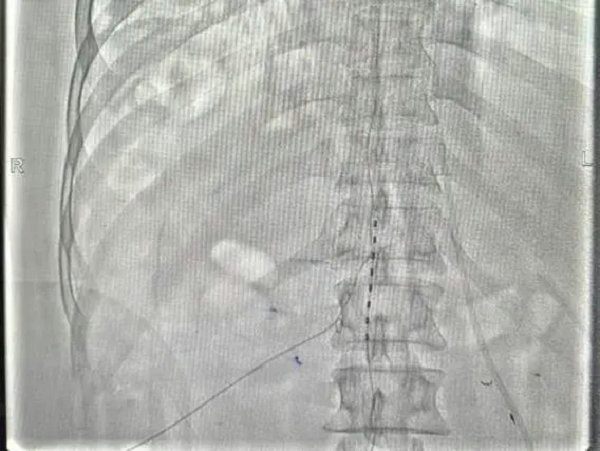

4月27日在医院复合手术室,由寿记新主任医师、管海博主治医师共同完成颈段及腰段短时程脊髓电极植入术,为患者尽早拔除气管套管、完全清醒、站起来、能走路、回归生活奠定了良好基础。

病例二:老年男性,1个月前“因高处坠落致颅脑及胸段脊髓损伤后双下肢截瘫”,由外院转入神经外科一病区,后经积极评估、讨论后给予胸段椎管扩大减压+内固定术。术后虽左下肢可稍活动,但右侧下肢仍无明显活动、大小便排便困难,需持续卧床,家属进行照顾。患者及家属治疗愿望迫切,1周前科室再次充分讨论下一步治疗方案,最后决定行腰段短时程脊髓电刺激手术治疗。